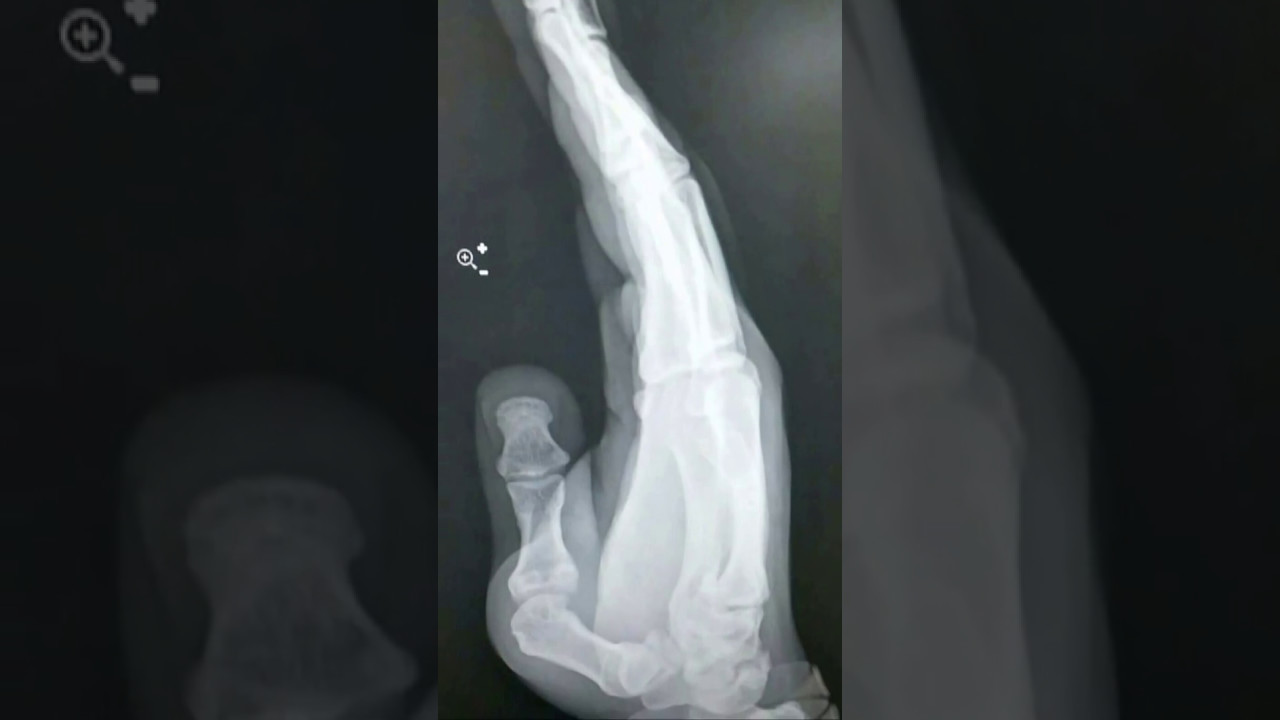

Xray of hand showing thumb dislocation Stock Photo Alamy Thumb Dislocation Healing Time But it can take up to six months for your finger to fully heal. Put ice or a cold pack on your thumb for 10 to 20 minutes at a time. Following medical treatment, dislocated fingers usually take a few weeks to heal. In some cases, especially when the dislocation is accompanied by a serious break or medical treatment is. Thumb Dislocation Healing Time.